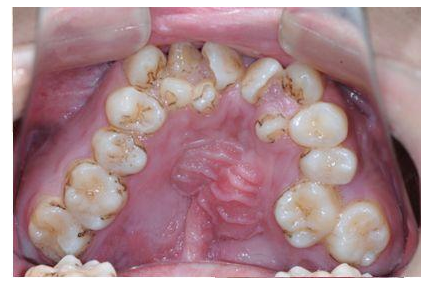

全民矫牙公益行动牙不齐的危害有哪些

牙齿不齐的危害

3影响牙体及牙周组织的健康

4影响口腔卫生护理

牙齿排列不齐会影响牙齿清洁,易堆积食物残渣,导致牙石形成、牙龈红肿、萎缩和牙槽嵴吸收,严重时甚至会导致牙齿松动。